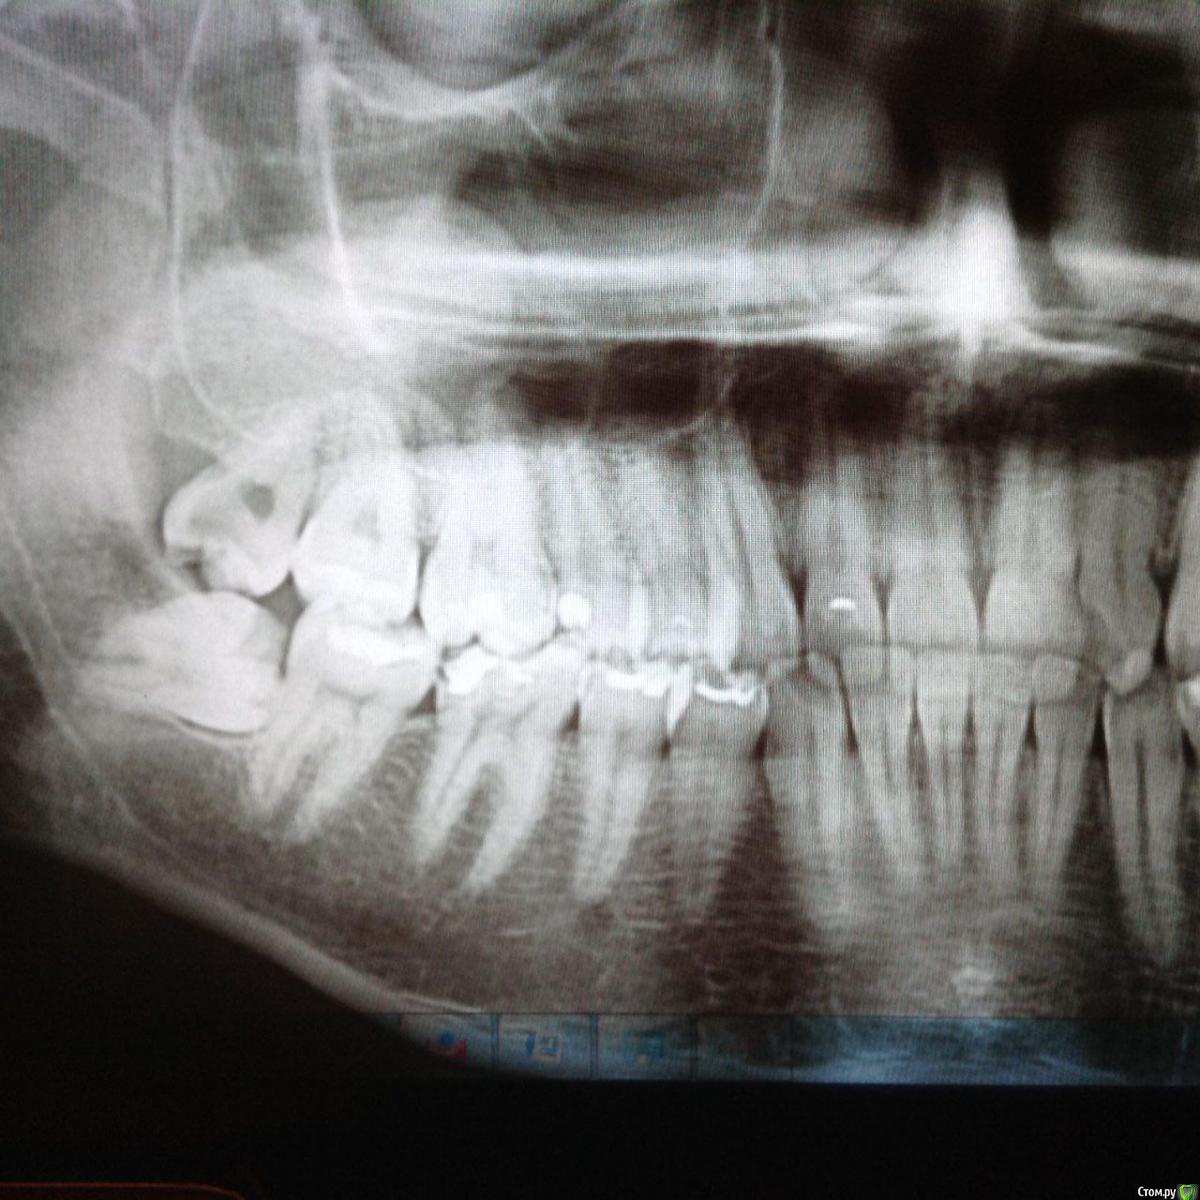

Света88888 Опубликовано 12 августа, 2015 Поделиться Опубликовано 12 августа, 2015 Добрый день, уважаемые Гуру! Пожалуйста, подтвердите, или опровергните, заключение, что все 3 зуба мудрости являются ретинированными.Очень интересует ваше мнение насчет правой восьмерки. Зуб полностью прорезался. Спасибо! Ссылка на комментарий

red_butler Опубликовано 12 августа, 2015 Поделиться Опубликовано 12 августа, 2015 низ - ретинированные, дистопированные, если их частично видно, то полу ретинированные. Верх, скорее всего дистопированный. Все удалять 3 Ссылка на комментарий